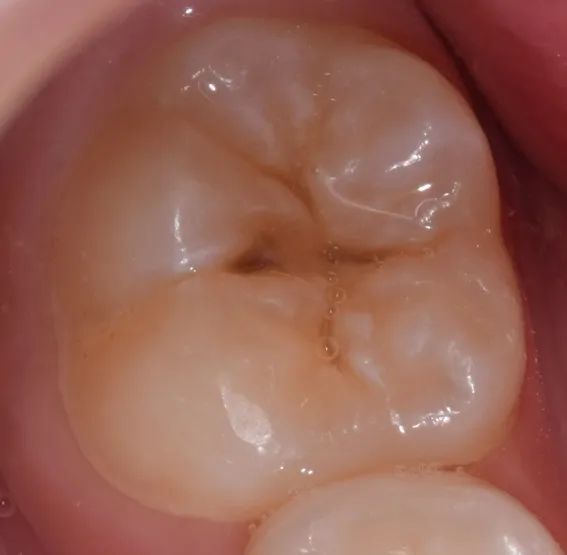

一是,牙齿发生龋坏,俗称虫牙:

二是,牙面色素沉着:

但这两种情况需要齿科医生检查确认,再制订后续计划。

如果是发生龋坏,须先把龋坏去掉,并做充填(补牙)等治疗修复牙齿硬组织。然后,如果这颗牙还存在没龋坏的窝沟,那么可以做窝沟封闭。

如果只是色素沉着,经过适度清洁后可以做窝沟封闭。